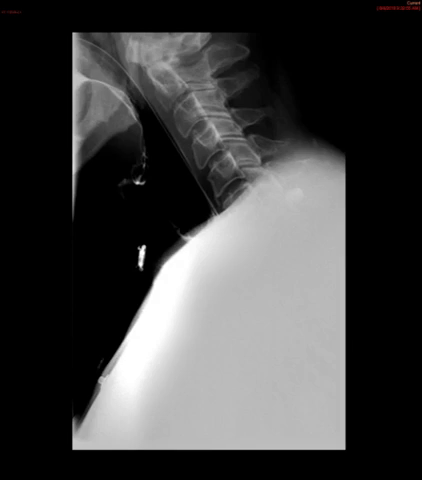

- Method—Cervical:

- Start with the patient in the upright lateral position.

- Once the patient has taken the "comfortable mouthful" of barium, center the fluoroscope on the cervical esophagus.

- Once the fluoroscope is properly positioned, begin counting. On the count of 2, begin taking rapid sequence images of the contrast material bolus as it moves through the cervical esophagus

(key image 1)